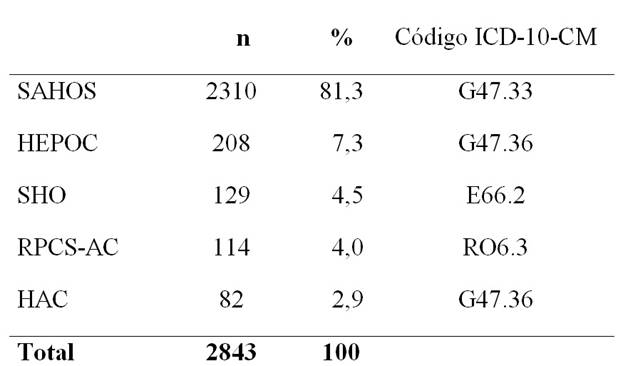

Se diagnosticó un trastorno respiratorio del sueño en 2843 pacientes (91,4%); un trastorno del sueño no respiratorio en 266 (7,2%) y en 42 los síntomas fueron inespecíficos y el estudio del sueño fue normal o insuficiente (1,4%). Los trastornos respiratorios del sueño se presentan catalogados en cinco grupos (Tabla 1). Si bien existió superposición de diagnósticos y asociación con trastornos del sueño no respiratorios, para este cálculo se consideró el trastorno predominante que condujo el diagnóstico y la terapéutica.

Tabla 1: Pacientes con trastornos respiratorios del sueño

Tabla 1. Grupos diagnósticos de 2843 pacientes con trastornos respiratorios del sueño, de un total de 3109 referidos. SAHOS: Síndrome de Apneas-Hipopneas Obstructivas del Sueño; HEPOC: Hipoxemia durante el Sueño en la EPOC ; RPCS-AC: Respiración Periódica de Cheyne-Stokes-Apneas Centrales; SHO: Síndrome de Hipoventilación-Obesidad; HAC: Hipoventilación Alveolar Crónica por Trastorno Neuro-Músculo-Esquelético.

Se presentan los resultados de los pacientes con SAHOS, de acuerdo a la definición sindromática: presencia de somnolencia excesiva diurna persistente, asociada a más de 5 apneas o hipopneas obstructivas por hora de sueño.